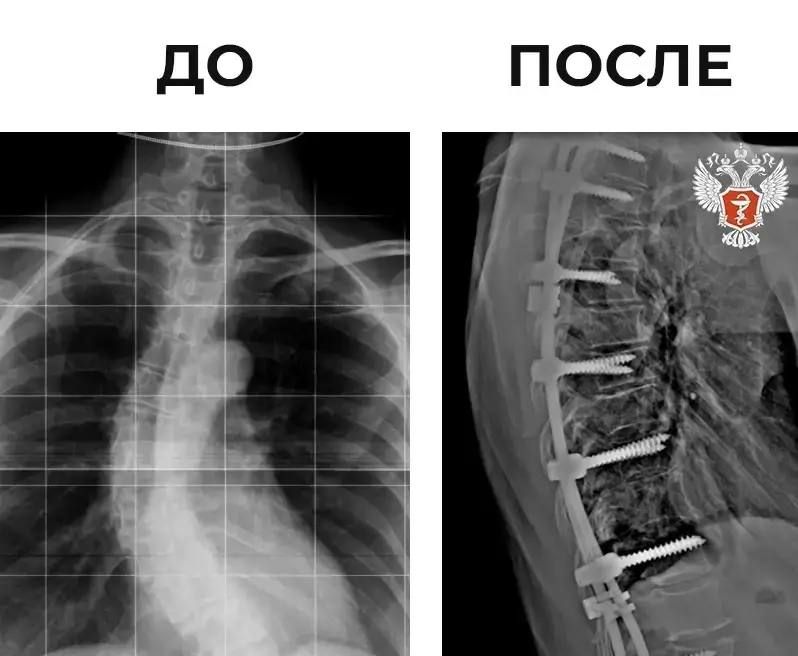

57-летняя женщина поступила в Клиническую больницу скорой медицинской помощи им. Н.В. Соловьева с S-образной деформацией позвоночника и постоянными болями в спине.Долгое время пациентка не обращалась за медицинской помощью и состояние постепенно...